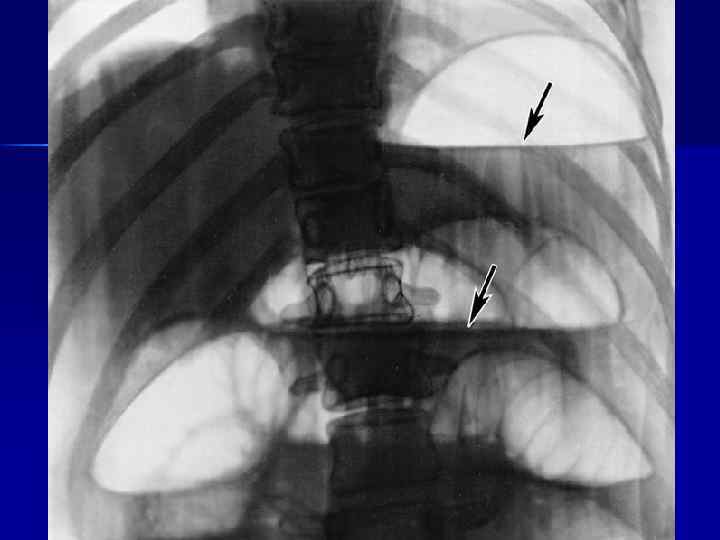

Рентгенологическое исследование

Кишечные аркады. Получаются, когда тонкая кишка оказывается раздутой газами, при этом в нижних коленах аркад видны горизонтальные уровни жидкости. Симптом перистости (поперечная исчерченность в форме растянутой пружины) встречается при высокой кишечной непроходимости и связан с растяжением тощей кишки, имеющей высокие циркулярные складки слизистой. на фоне раздутых газом петель тонкой кишки (1) с уровнями жидкости в них (2) видна поперечная исчерченность (3), придающая петлям вид пружин.